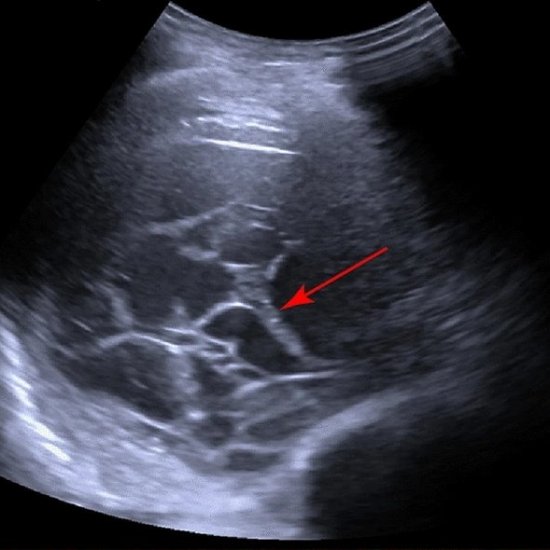

Artikel • Neue Stärken, Abhilfe für alte Schwächen

Ist die Organ-Bildgebung per Ultraschall auf dem gleichen Niveau wie die Schnittbildgebung angekommen? Auf der Jahreskonferenz der Deutschen Gesellschaft für Innere Medizin (DGIM) stellte PD Dr. Corinna Trenker neue technologische Entwicklungen und ... |